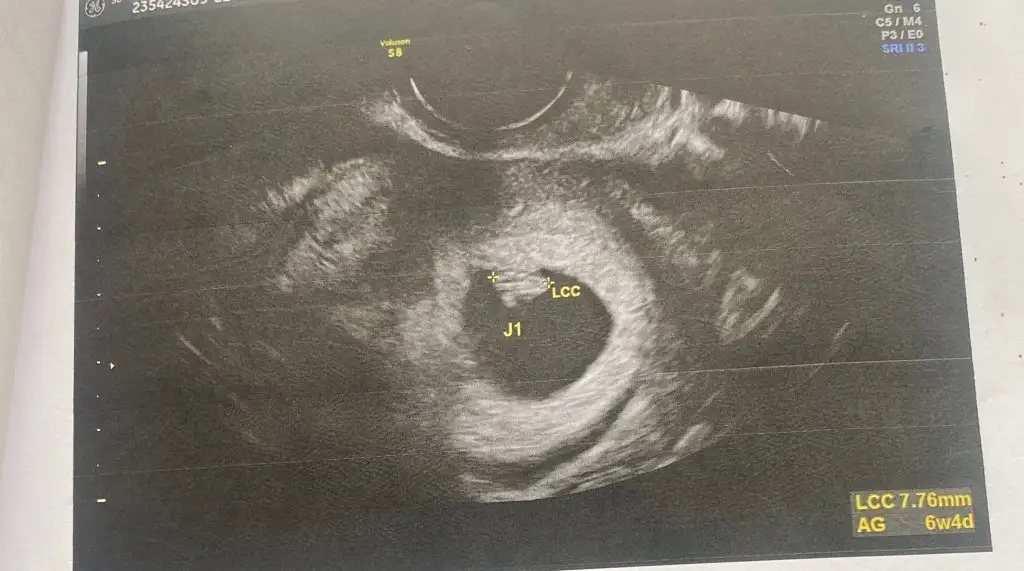

Merhaba 6+5 çift yumurta ikizleri (iki ultrasonda ayrı )vajinal muayane 3. Fotoda iki kese görünüyor